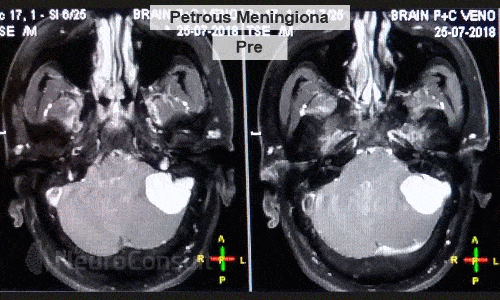

I am an consultant neurosurgeon. I have completed my Masters in General Surgery from SN Medical College, Agra and thereafter completed my formal Neurosurgical training from one of India's premier institute ie. SREE CHITRA TIRUNAL INSTITUTE OF SCIENCES AND TECHNOLOGY, Trivandrum (An institute of national importance). I have special interest in brain and spinal tumors.

I've been involved in numerous treatment of brain and spine-related ailments like spinal joint and disc disease, brain infarction(stroke/paralysis), hydrocephalus etc. to name the few. I am passionate about patient care and strives very hard for their recovery both physically and mentally.